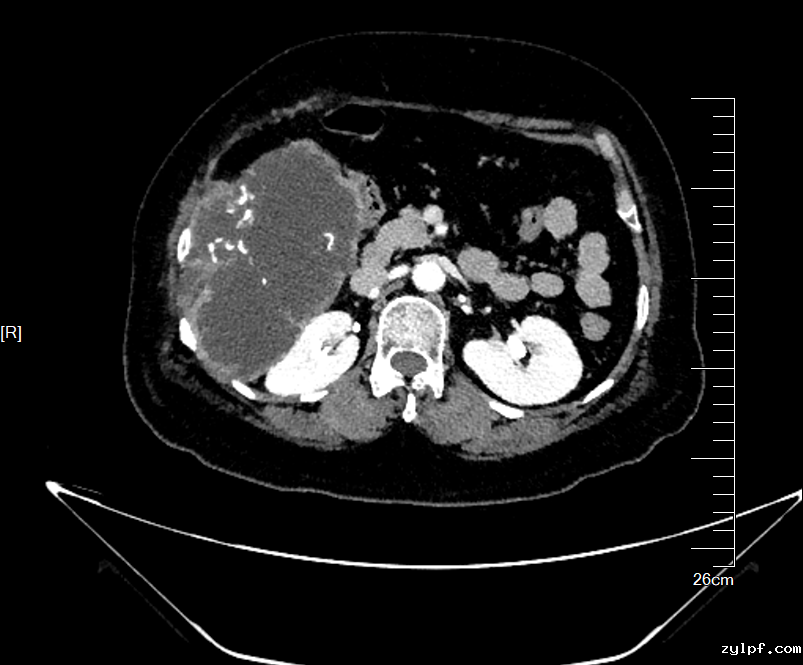

术前CT评估肿物与周围脏器关系,横截面与冠状面

影像检查显示,肿物起源于第7,8肋骨,沿胸腹壁蔓延累及第7至第11肋,上界与肝脏S5、S6段分界不清,内侧包膜紧贴右侧结肠,后方逼近右肾。“患者首次手术已切除部分肋骨,此次复发范围更广、侵袭更深,既要确保肿瘤完整切除(R0切除),又要最大限度保护重要脏器,需要多学科专家协作和新技术手段保驾护航。”骨科王伟东副主任在初次讨论时指出了本案例的关键节点。